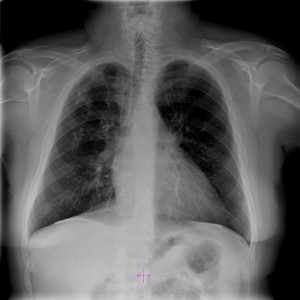

Hemotórax

El objetivo del tratamiento es estabilizar al paciente, detener el sangrado y extraer la sangre y el aire del espacio pleural. Se introduce una sonda pleural a través de la pared del tórax con el fin de drenar la sangre y el aire. La sonda se deja puesta durante varios días para volver a expandir el pulmón.